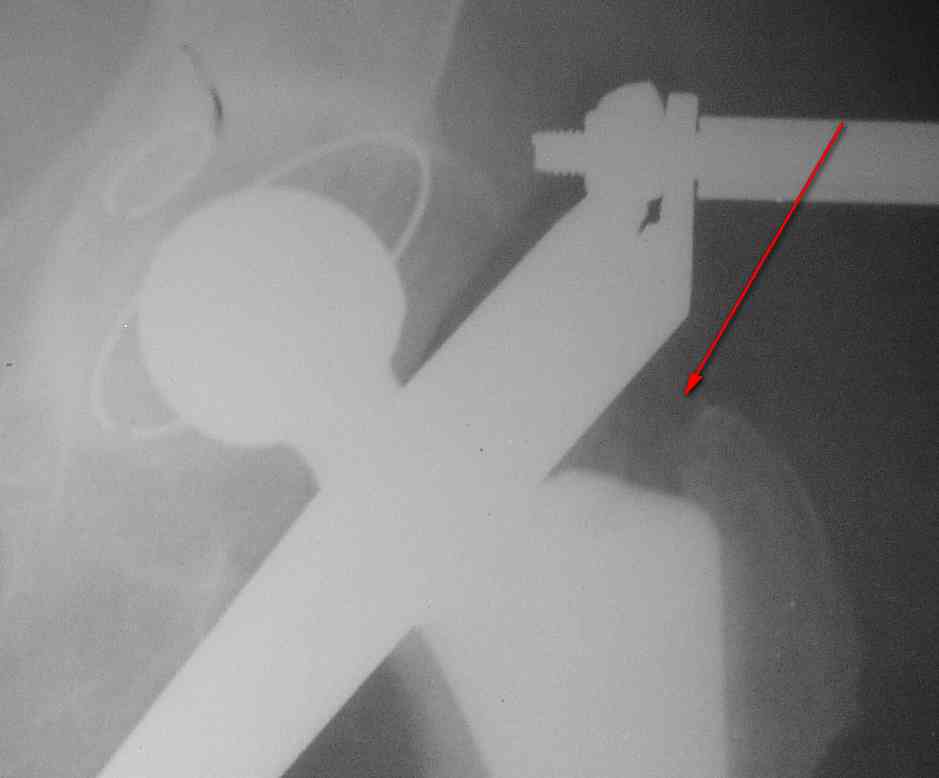

1. На снимке №3 не видны ни проксимальный отдел бедра с зоной (линией) перелома

Там видно расхождение фрагментов, диастаз чуть медиальнее б. вертела.

Снимок №4 демонстрирует дистальную линию перелома, но не показывает уровень конца ножки эндопротеза.

Кончик ножки виден на самом верху этого снимка.

Вот фрагменты этих снимков с более различимыми областями интереса.

Видимо, тут надо добиваться точной репозиции этой спирали вдоль протеза, чтобы воссоздать ложе для ножки.